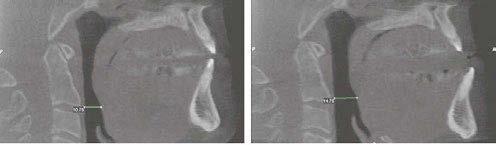

Here’s more good news. In this issue of Dental Sleep Practice, our Cover Story spotlights the latest in dental sleep medi cine solutions to treat OSA patients more effectively. SomnoMed’s second annual SomSummit focused on vetting the value of all sleep therapies and explored the fun damental research that supports them in improving, and even defining, OSA treat ment success. In our CE, “Interarch Jaw Registration Devices for Oral Sleep Appli ances,” Dr. Allen J. Moses explains bilat eral molar stabilization and creating a more open airway. In “Tongue Tie is Not Your Only

the patient that revealed symptoms of severe sleep bruxism, excessive daytime sleepiness, and snoring. The patient also complained of having chronic pain in the jaw and masseters, especially when waking up in the mornings. He reported gaining over 10 pounds in the last few years and the presence of hyperten sion which was not responsive to his daily medication.

The patient was referred to complete an in-lab polysomnogram (PSG) since it had been a long time since his previous sleep study.

The results of the PSG indicated the pres ence of severe OSA with an apnea/hypopnea index (AHI) of 43.1/Hr and respiratory dis turbance index (RDI) of 44.8/Hr. The PSG also indicated a REM dom inant OSA with an AHI of 58.6/Hr. The minimum SaO2 was 89.0% with a mean SaO2 of 98.8%. The sleep efficiency was cal culated at 93.4%.

Despite his severe OSA, the patient refused treatment with CPAP and was referred back to Dr. Yousefian’s office to be treated for his OSA and masticatory/temporoman dibular joint disorders (M/ TMJD). His treatment was initiated with bedtime use of the ApnoDent®, an FDA-approved oral appliance (Figure 2) designed to manage his bruxism, M/TMJD issues, snoring, and OSA.

An efficacy test was performed after four weeks of ApnoDent® use; the sleep test results indicated a reduction of AHI to 1.9/Hr with SpO2 nadir of 91%. The Mean SaO2 was 94.7%, and the sleep efficiency was 93.4%

The patient started his 2-year supervision phase and continued to use the ApnoDent

with a lower clear retainer at bedtime.